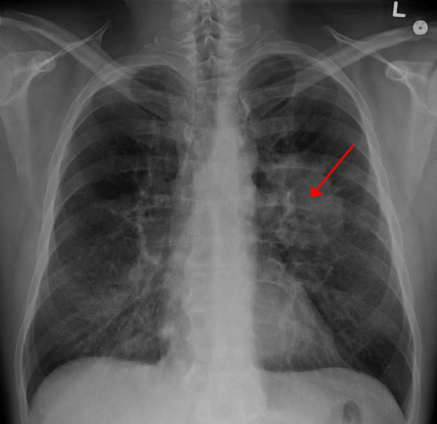

Clinical Oncologist at the Korle Bu Teaching Hospital, Dr Nana Ama Wadee, has raised concern over Ghana’s rising lung cancer deaths, warning that many patients are dying because the disease is often detected too late.

Speaking on Joy FM’s Super Morning Show on Thursday, October 16, as part of Joy Cancer Awareness Month, Dr Wadee explained that while lung cancer is the leading cause of cancer deaths worldwide, Ghana’s situation is particularly troubling because most patients report to the hospital when the disease is already advanced.

“In Ghana, lung cancer currently ranks about ninth or tenth in incidence, but the mortality almost mirrors the incidence,” she said. “As many patients as we see are dying, which reflects the late stage of presentation at which they come.”

“We believe there are a lot of underdiagnosed cases,” she said. “Many patients are treated over and over again for other respiratory conditions such as tuberculosis or pneumonia before it is eventually found to be lung cancer.”

She said that the early stages of lung cancer show no clear symptoms, making awareness and suspicion vital.

“Early lung cancer can be completely asymptomatic. When symptoms appear, patients may have a cough, breathlessness, chest pain, or cough up blood.”